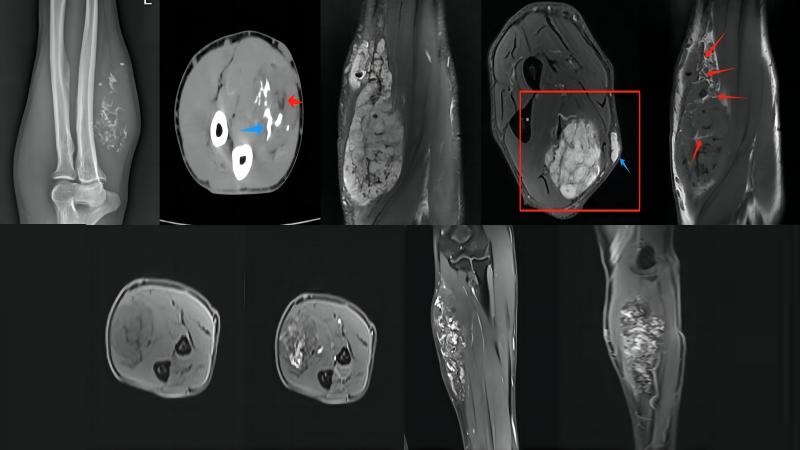

影像表现:x线:左尺骨内侧软组织内见多发斑点状及网状分支状致密影,软组织显著肿胀。CT:左前臂尺侧见团块状异常密度影,其内见多发小结节状、不规则条片状致密影,间隙内夹杂脂肪密度影。MR:左前壁内侧肌腱隙及皮下脂肪层内见大片蔓状生长异常信号,边界不清,形态不规则,T1WI呈低信号,夹杂条片状高信号,T2WI呈高低混杂信号,增强由轴位到矢状位再到冠状位顺序,呈渐进性明显强化。

病理:(左前臂)符合肌间血管瘤,瘤组织呈多灶性分布,管壁平滑肌增生伴玻璃样变性,局部可见钙化及骨化。

X线平片、CT :1.软组织增厚或肢体增粗,皮下脂肪层和肌肉内密度不均。2. 如发现静脉石具有诊断意义,典型静脉石为中空的钙化密度影。3.CT在显示病变内出血、钙化、静脉石及邻近骨质受侵等方面更加有优势。

MRI :1.血管成分表现为T1WI等至稍高信号, T2WI明显高信号 。2.非血管成分则因组织构成不同而表现为信号不一 , 纤维脂肪分隔、透明变性和发生血栓的血管,可于T2WI表现为中心低信号(具有特征性) 。3.增强扫描明显强化,脂肪、纤维分隔等非血管组织无强化。